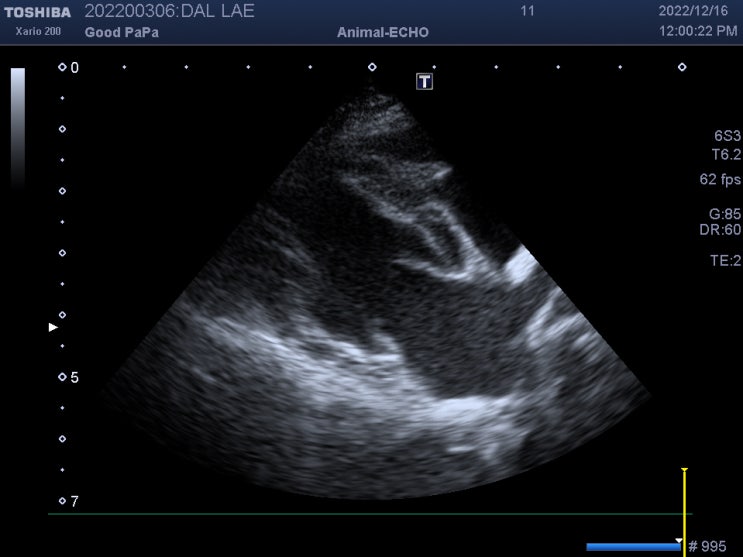

심장병 있는 강아지 집에서 관리 & 주의 사항 / 13살 푸들 강아지 심장병 3년 관리 후기 / 반려견 심장 전문 동물병원 / 댕댕이 심장병 걸리면 얼마나 사나요?

안녕하세요~ 굿파파 수의사입니다. 오늘 오후는 많이 덥네요~^^* 시원한 커피 한 잔과 함께 행복한 미소 가...